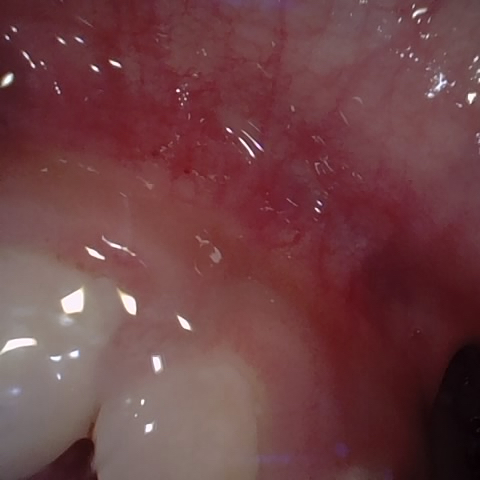

Annotated as "Bad"